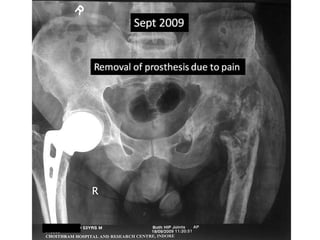

Case summary •Persistent pain in hip and knee since revision. • Hip ultra-sonography in April 2009 – small pocket – aspiration negative. • No relief with antibiotics. • Removal of Solution hip in Sept 2009.

• Persistent pain in hip and knee since revision.

• Hip ultra-sonography in April 2009 – small

pocket – aspiration negative.

• No relief with antibiotics.

• Removal of Solution hip in Sept 2009.